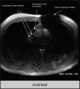

Parasellar signal void

May Be Caused by

Basilar tip aneurysm

Carotid-cavernous fistula

Cavernous carotid aneurysm

Densely calcified meningioma

Kissing carotids

Pneumatized posterior clinoid

Supraclinoid carotid aneurysm